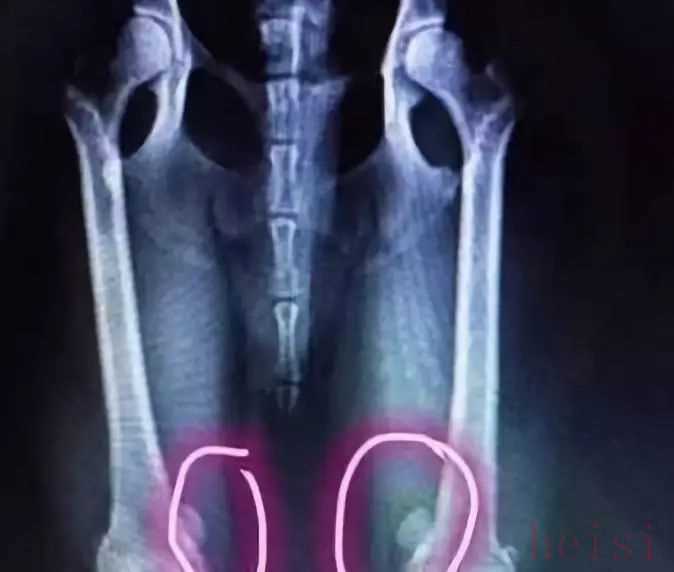

殊不知,后腿長期承受壓力,會導致脫臼。